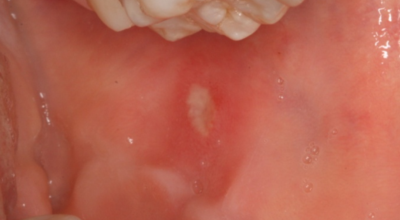

입안 점막이 동그랗게 패여 통증을 유발한다면, 아프타성 구내염을 의심할 수 있어요. 음식을 먹을 때마다 아픈 작은 궤양이 생겼다면, 아프타성 구내염을 의심할 수 있어요. 아프타성 구내염은 빨간색 둘레를 가진 둥근 형태의 흰색 궤양이, 얕은 깊이로 한 개 및 여러 개 생기며 통증을 동반하는 것이 특징입니다. 전 인구의 20~40%가 발병할만큼 통상적으로 나타나는 질환으로 20대, 주로 여성분들에게 많이 나타나며, 일주일 정도면 자연적으로 치유되지만 1~3개월 간격으로 빈번히 재발하는 것이 특징입니다.